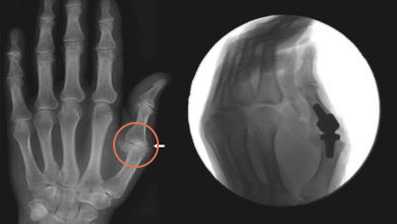

Эндопротезирование запястно-пястного сустава первого пальца кисти

Эндопротез запястно-пястного сустава 1 пальца кисти представляет собой несвязанный эндопротез, состоящий из проксимального и дистального компонентов. Материалом изготовления служит циркониевая керамика.